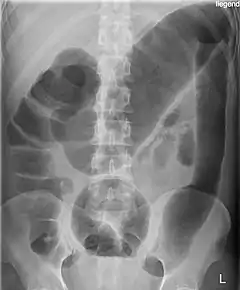

![]() Radiografía del abdomen de un paciente afecto de megacolon tóxico secundario a colitis ulcerosa. | ||